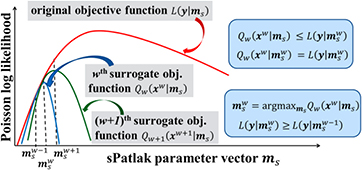

The nested 4D sPatlak image reconstruction algorithm breaks down the previous integrated EM process into two steps: (i) a single tomographic projection-based EM update of the dynamic image estimates, based on the measured 4D data, followed by (ii) multiple nested image-based EM updates of the kinetic parameter estimates, based on the dynamic image estimates from step 1. The nested ML-EM implementation utilizes the 'optimization transfer' principle (Lange et al 2000), which 'transfers' the optimization target from a single and more complex global objective function to simpler surrogate functions, that vary at each global ML-EM iteration step, as illustrated in figure 3 (Carson and Lange 1985, Wang and Qi 2010, 2012, 2013, Karakatsanis and Rahmim 2014a).

Figure 3. (Left) Diagram of ML-EM global objective function  (red curve) and surrogate functions

(red curve) and surrogate functions  (blue) and

(blue) and  (green) for global iterations

(green) for global iterations  and

and  , respectively. They all are Poisson log-likelihood functions depending on the sPatlak parameter vector

, respectively. They all are Poisson log-likelihood functions depending on the sPatlak parameter vector  . The basic principles of optimization transfer are illustrated as follows: (a) each value of the

. The basic principles of optimization transfer are illustrated as follows: (a) each value of the  th surrogate function is either lower or equal to the value of the global objective function at the same

th surrogate function is either lower or equal to the value of the global objective function at the same  . In addition, (b) the maximum value of

. In addition, (b) the maximum value of  th surrogate function is equal to the value of the global function at

th surrogate function is equal to the value of the global function at  . The set of parameters maximizing the

. The set of parameters maximizing the  th surrogate objective function is considered the optimal for

th surrogate objective function is considered the optimal for  th iteration, as described in (c). Finally,

th iteration, as described in (c). Finally,  yields higher values for the global objective function, as the iterations progress (d).

yields higher values for the global objective function, as the iterations progress (d).

Standard image High-resolution imageIn the nested sPatlak 4D ML-EM framework, both the global objective function  and the surrogate objective function

and the surrogate objective function  , for each iteration

, for each iteration  , are defined as Poisson log-likelihood functions of the measured dynamic data Y and the dynamic image estimate xw at iteration

, are defined as Poisson log-likelihood functions of the measured dynamic data Y and the dynamic image estimate xw at iteration  , respectively, given the sPatlak parameter vector

, respectively, given the sPatlak parameter vector  . In fact, the nested section of the sPatlak 4D ML-EM algorithm for global iteration

. In fact, the nested section of the sPatlak 4D ML-EM algorithm for global iteration  utilizes the latest dynamic image estimate xw from step 1 to return, after several sub-iterations, the ms parameter vector that maximizes the

utilizes the latest dynamic image estimate xw from step 1 to return, after several sub-iterations, the ms parameter vector that maximizes the  th iteration surrogate log-likelihood function

th iteration surrogate log-likelihood function  (figure 3(c)). Subsequently, the returned value

(figure 3(c)). Subsequently, the returned value  initializes the tomographic ML-EM update (step 1) of the next, i.e.

initializes the tomographic ML-EM update (step 1) of the next, i.e.  th iteration.

th iteration.

We note that our scheme employs an ML-EM optimization algorithm for both the external tomographic and the nested image-based iterative update processes, while the respective Poisson log-likelihood functions satisfy the criteria described in figures 3(a) and (b). In addition, the external and nested Poisson log-likelihood maximization problems described above are equivalent to minimizing the Kullback–Leibler (KL) distance metrics (Barrett and Myers 2004) between the measured dynamic data Y and dynamic images xw, for the tomographic estimation problem, and between the estimated dynamic images xw and the new sPatlak parameter estimates  for the image-based parametric estimation problem. Under these conditions, the 4D ML-EM nested estimation of the sPatlak parameters is legitimately performed, as the Poisson distribution in the measured counts is fully accounted, and the EM convergence of the nested 4D ML-EM algorithm is ensured, as illustrated in figure 3(d).

for the image-based parametric estimation problem. Under these conditions, the 4D ML-EM nested estimation of the sPatlak parameters is legitimately performed, as the Poisson distribution in the measured counts is fully accounted, and the EM convergence of the nested 4D ML-EM algorithm is ensured, as illustrated in figure 3(d).

Similarly with sPatlak, the presented nested gPatlak 4D algorithm targets at Poisson log-likelihood types of global and surrogate functions and employs the ML-EM algorithm for the external and the nested optimization problems. The main difference lies in the type of nested estimates targeted by the gPatlak algorithm. Due to the non-linear relationship between the gPatlak parameters and dynamic image space, the latter could not be estimated directly from the nested ML-EM approach employed in the previous section for nested sPatlak 4D case. Instead, the Patlak response vector rj at each voxel j is now estimated through the same nested ML-EM update process, as it is linearly related with the dynamic image estimates, according to equation (10b). Therefore, the same conditions apply to gPatlak case, as those illustrated in figure 3, if sPatlak parameter vector ms is replaced by the Patlak impulse response vector r. In fact, if kloss is set to zero, the gPatlak 4D formulation in equation (10b) reduces to the sPatlak framework and the direct linear relationship between parametric and dynamic image space is restored.